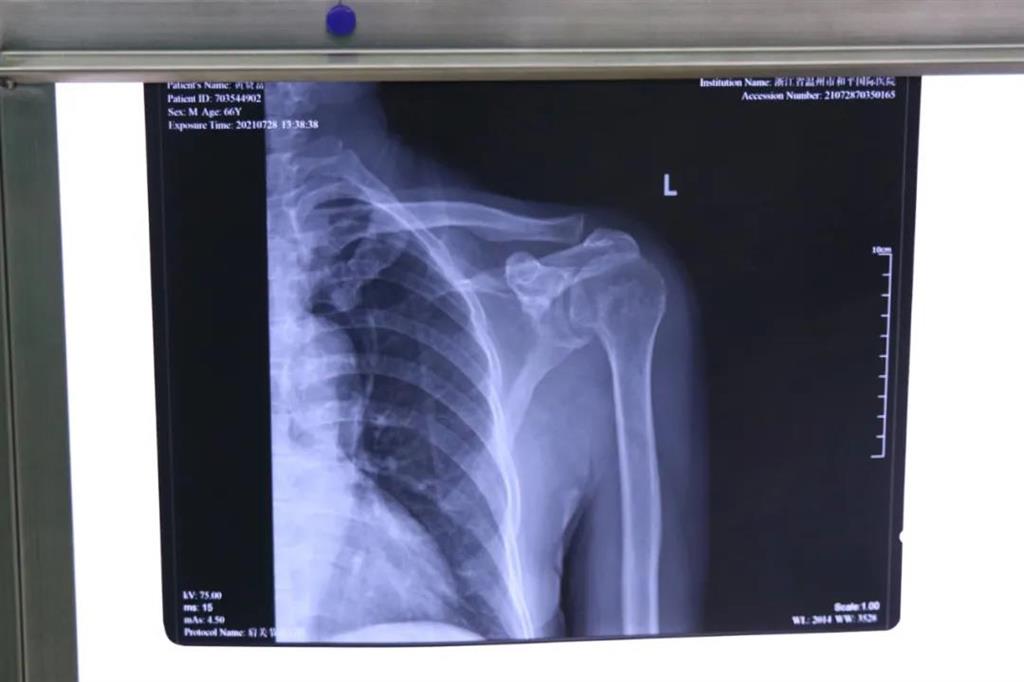

在和平國(guó)際醫(yī)院關(guān)節(jié)鏡微創(chuàng)團(tuán)隊(duì)的協(xié)作下,手術(shù)順利,成功用微創(chuàng)肩關(guān)節(jié)鏡進(jìn)行肩袖修補(bǔ)術(shù)。術(shù)中、術(shù)后患者幾無(wú)出血,且手術(shù)切口小,美觀,患者左肩部疼痛得到明顯緩解。